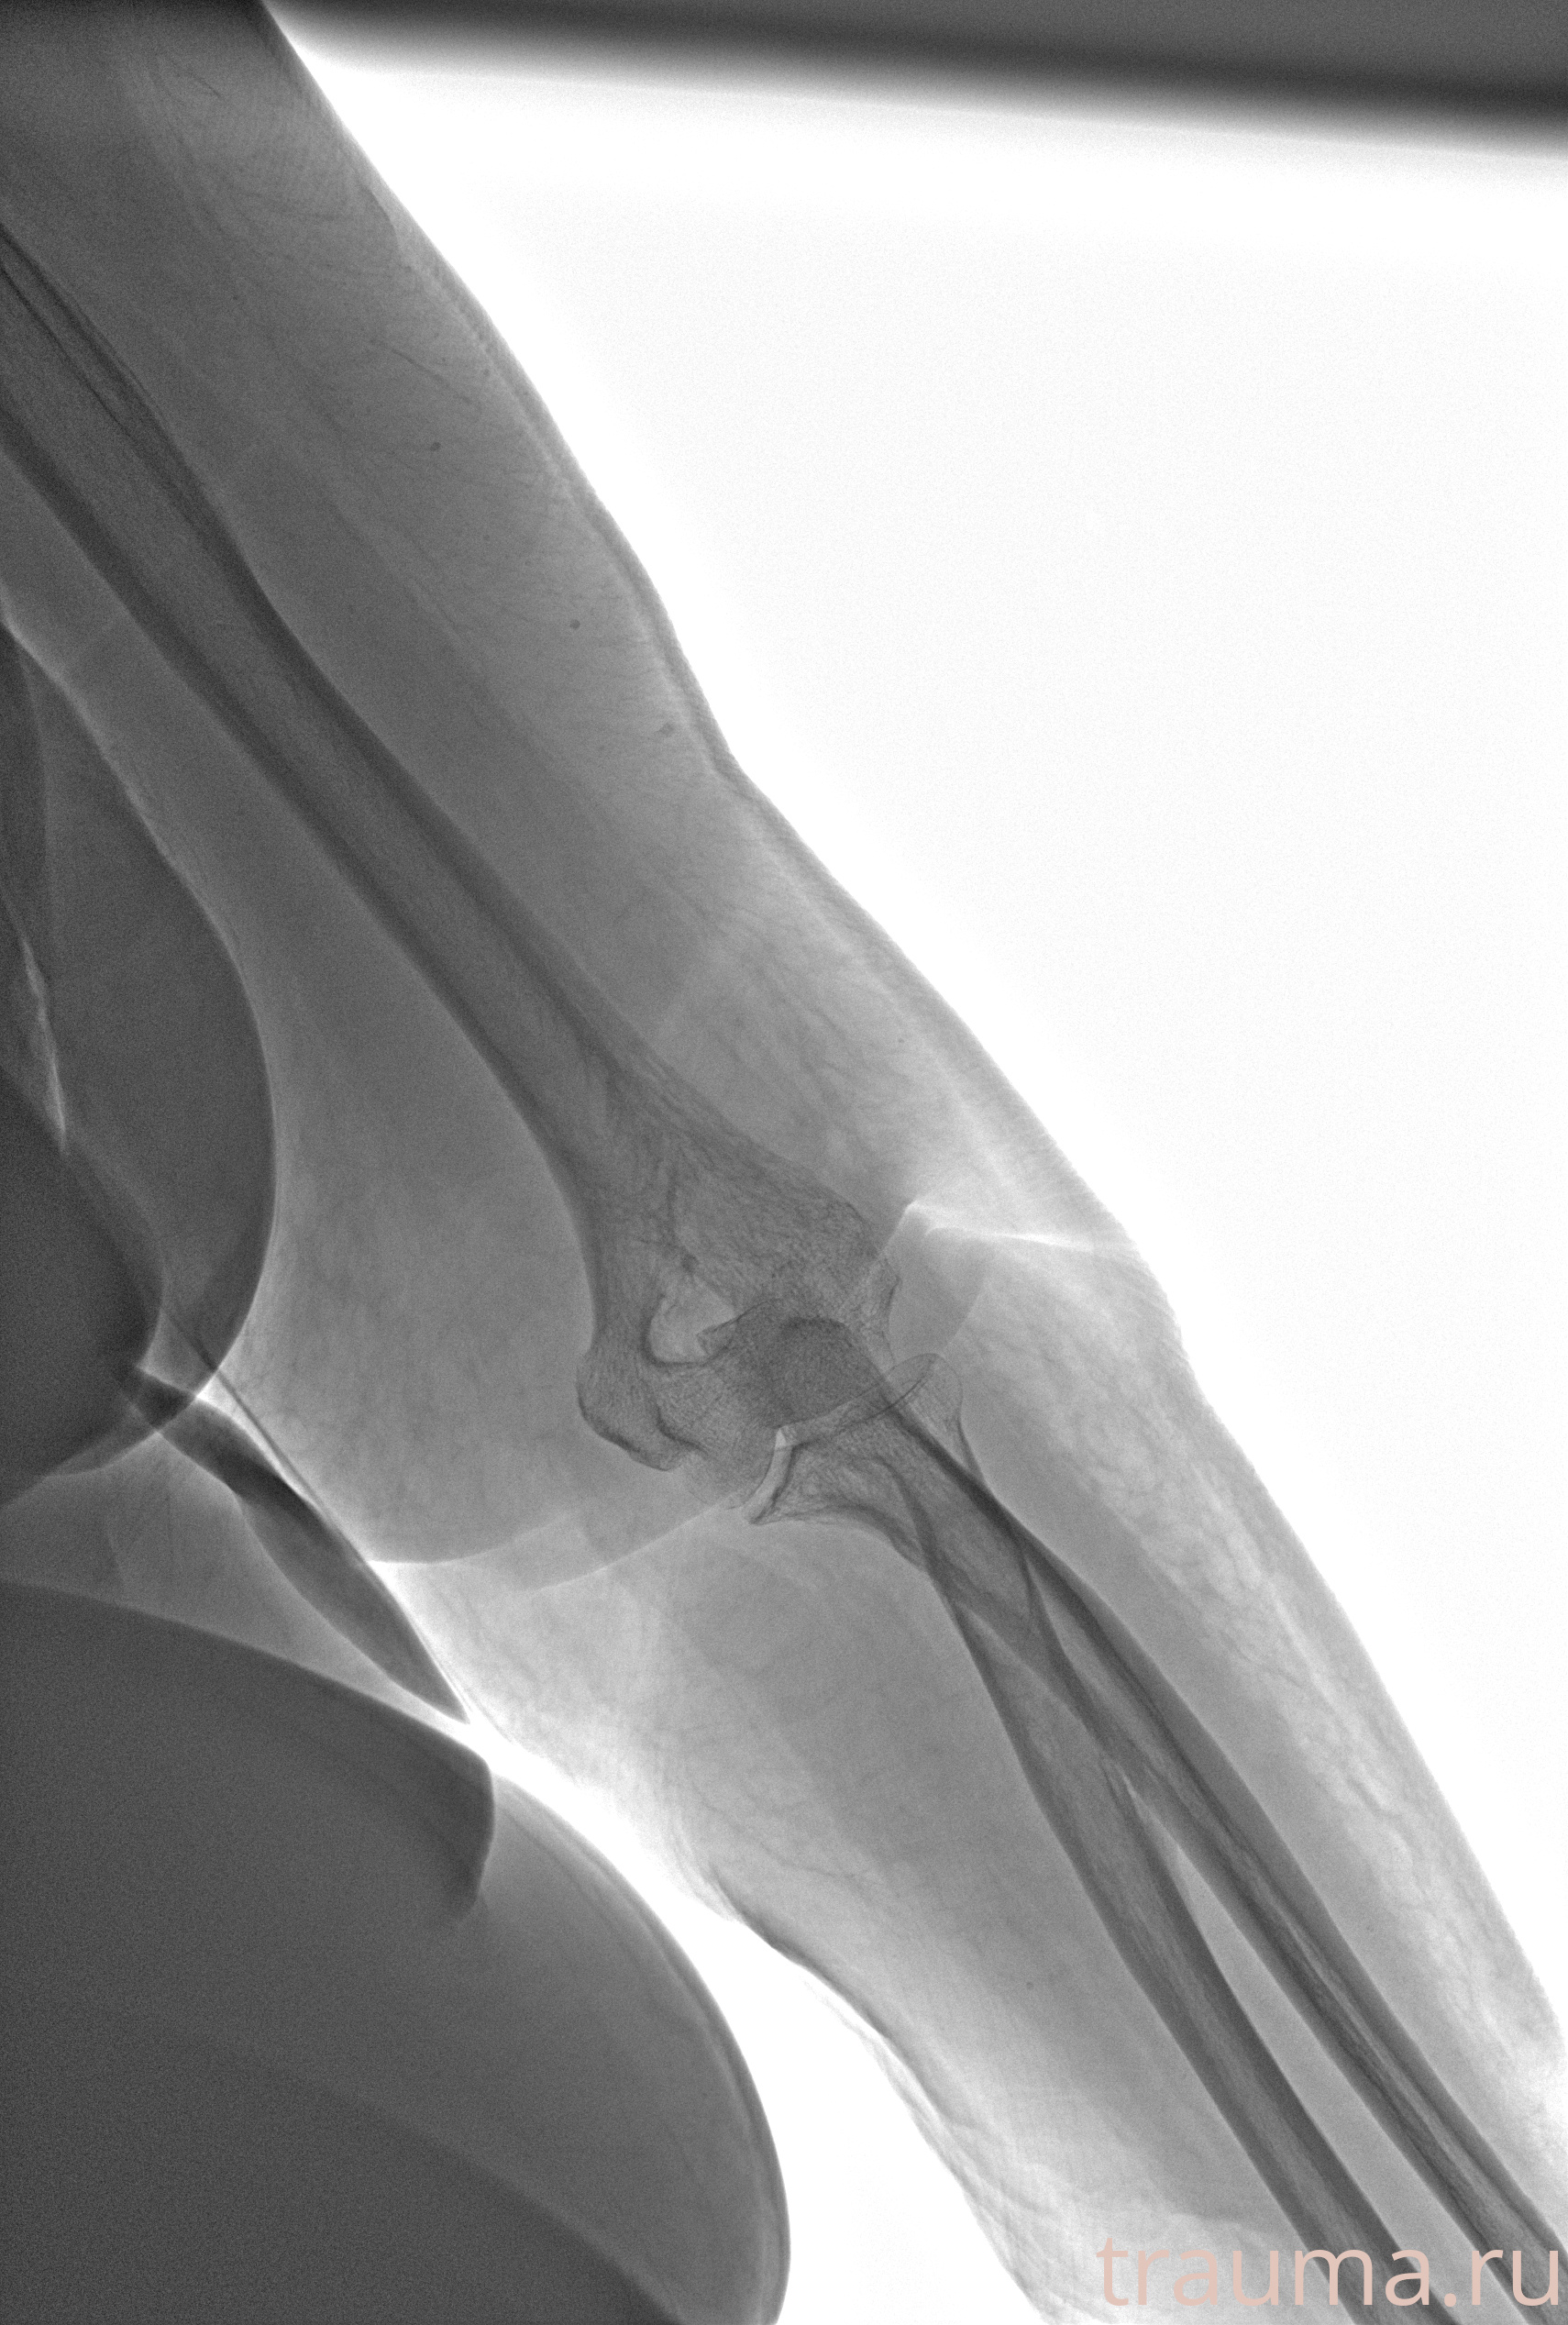

Рентген на дому: по вашему адресу приезжает врач-рентгенолог, травматолог-ортопед с мобильным рентгеновским аппаратом, проводит диагностику травмы или заболевания, делает необходимые рентгенограммы, дает рекомендации по дальнейшему лечению. Получить качественные снимки в домашних условиях возможно благодаря уникальной методике, разработанной МосРентген Центром для института  Склифосовского